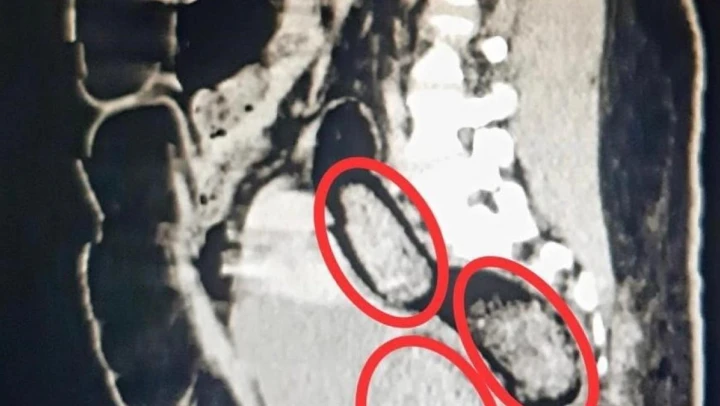

Otobüste gözaltına alınan Hadıs Aeınezad'in yapılan iç beden muayenesinde bağırsaklarında cisim olduğu tespit edildi. Hadıs Aeınezad'ın makadına saklanmış bir şekilde 3 parça 318 gram metamfetamin uyuşturucu maddesi cerrahi müdahaleyle çıkarıldı.